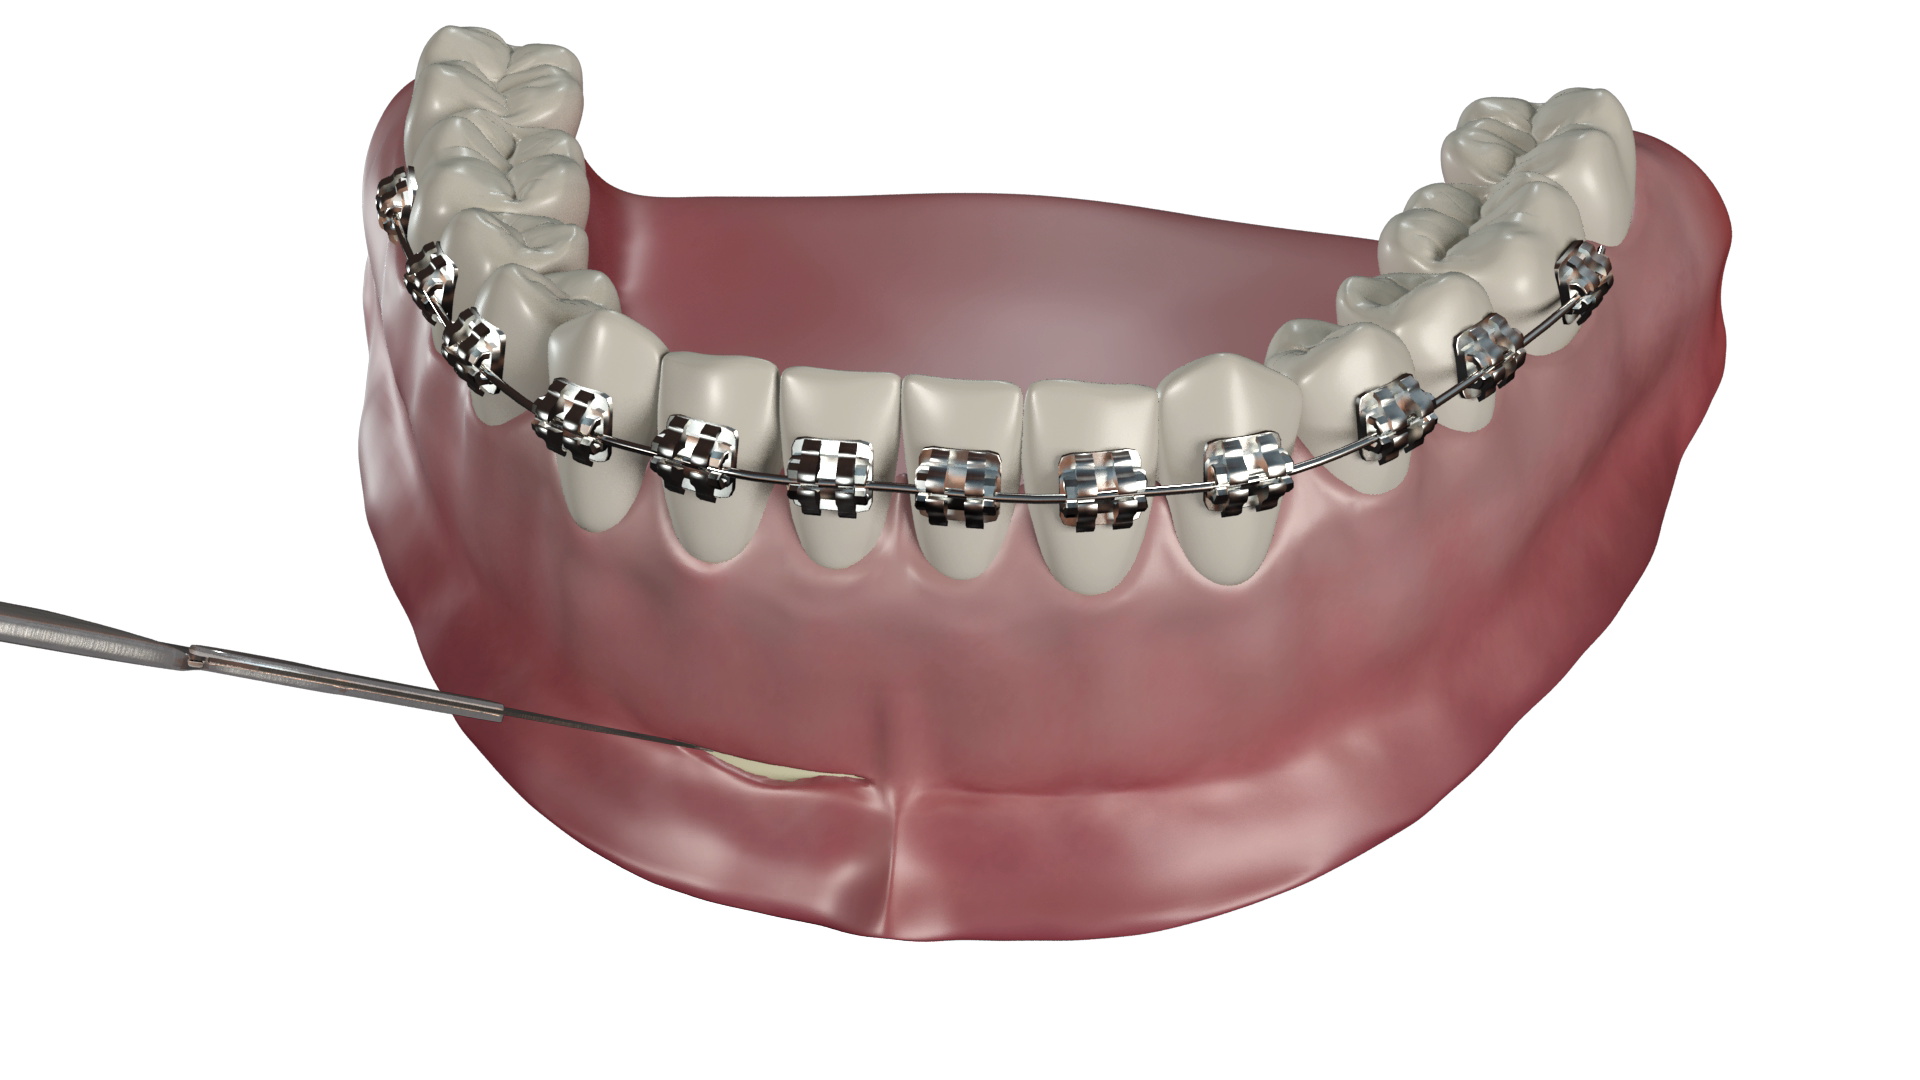

- Mise en forme du fil

Il longe la surface muqueuse sans la comprimer depuis le fond du vestibule, puis est façonné en ressort ou simplement replié en crochet pour pouvoir être relié à l’appareil ou directement aux les dents à déplacer.

L’appui sur deux vis permet d’obtenir une action 3D.

Le système peut être actif ou passif :

- Il est actif si le bras est déformé pour exercer une force dans la direction souhaitée. Sa longueur peut être importante et permettre ainsi d’agir sur une grande amplitude avec une force constante et contrôlée.

- Il est passif si le fil est droit et relié aux dents par une ligature élastique (ancrage direct) ou s’il renforce un ancrage (ancrage indirect).